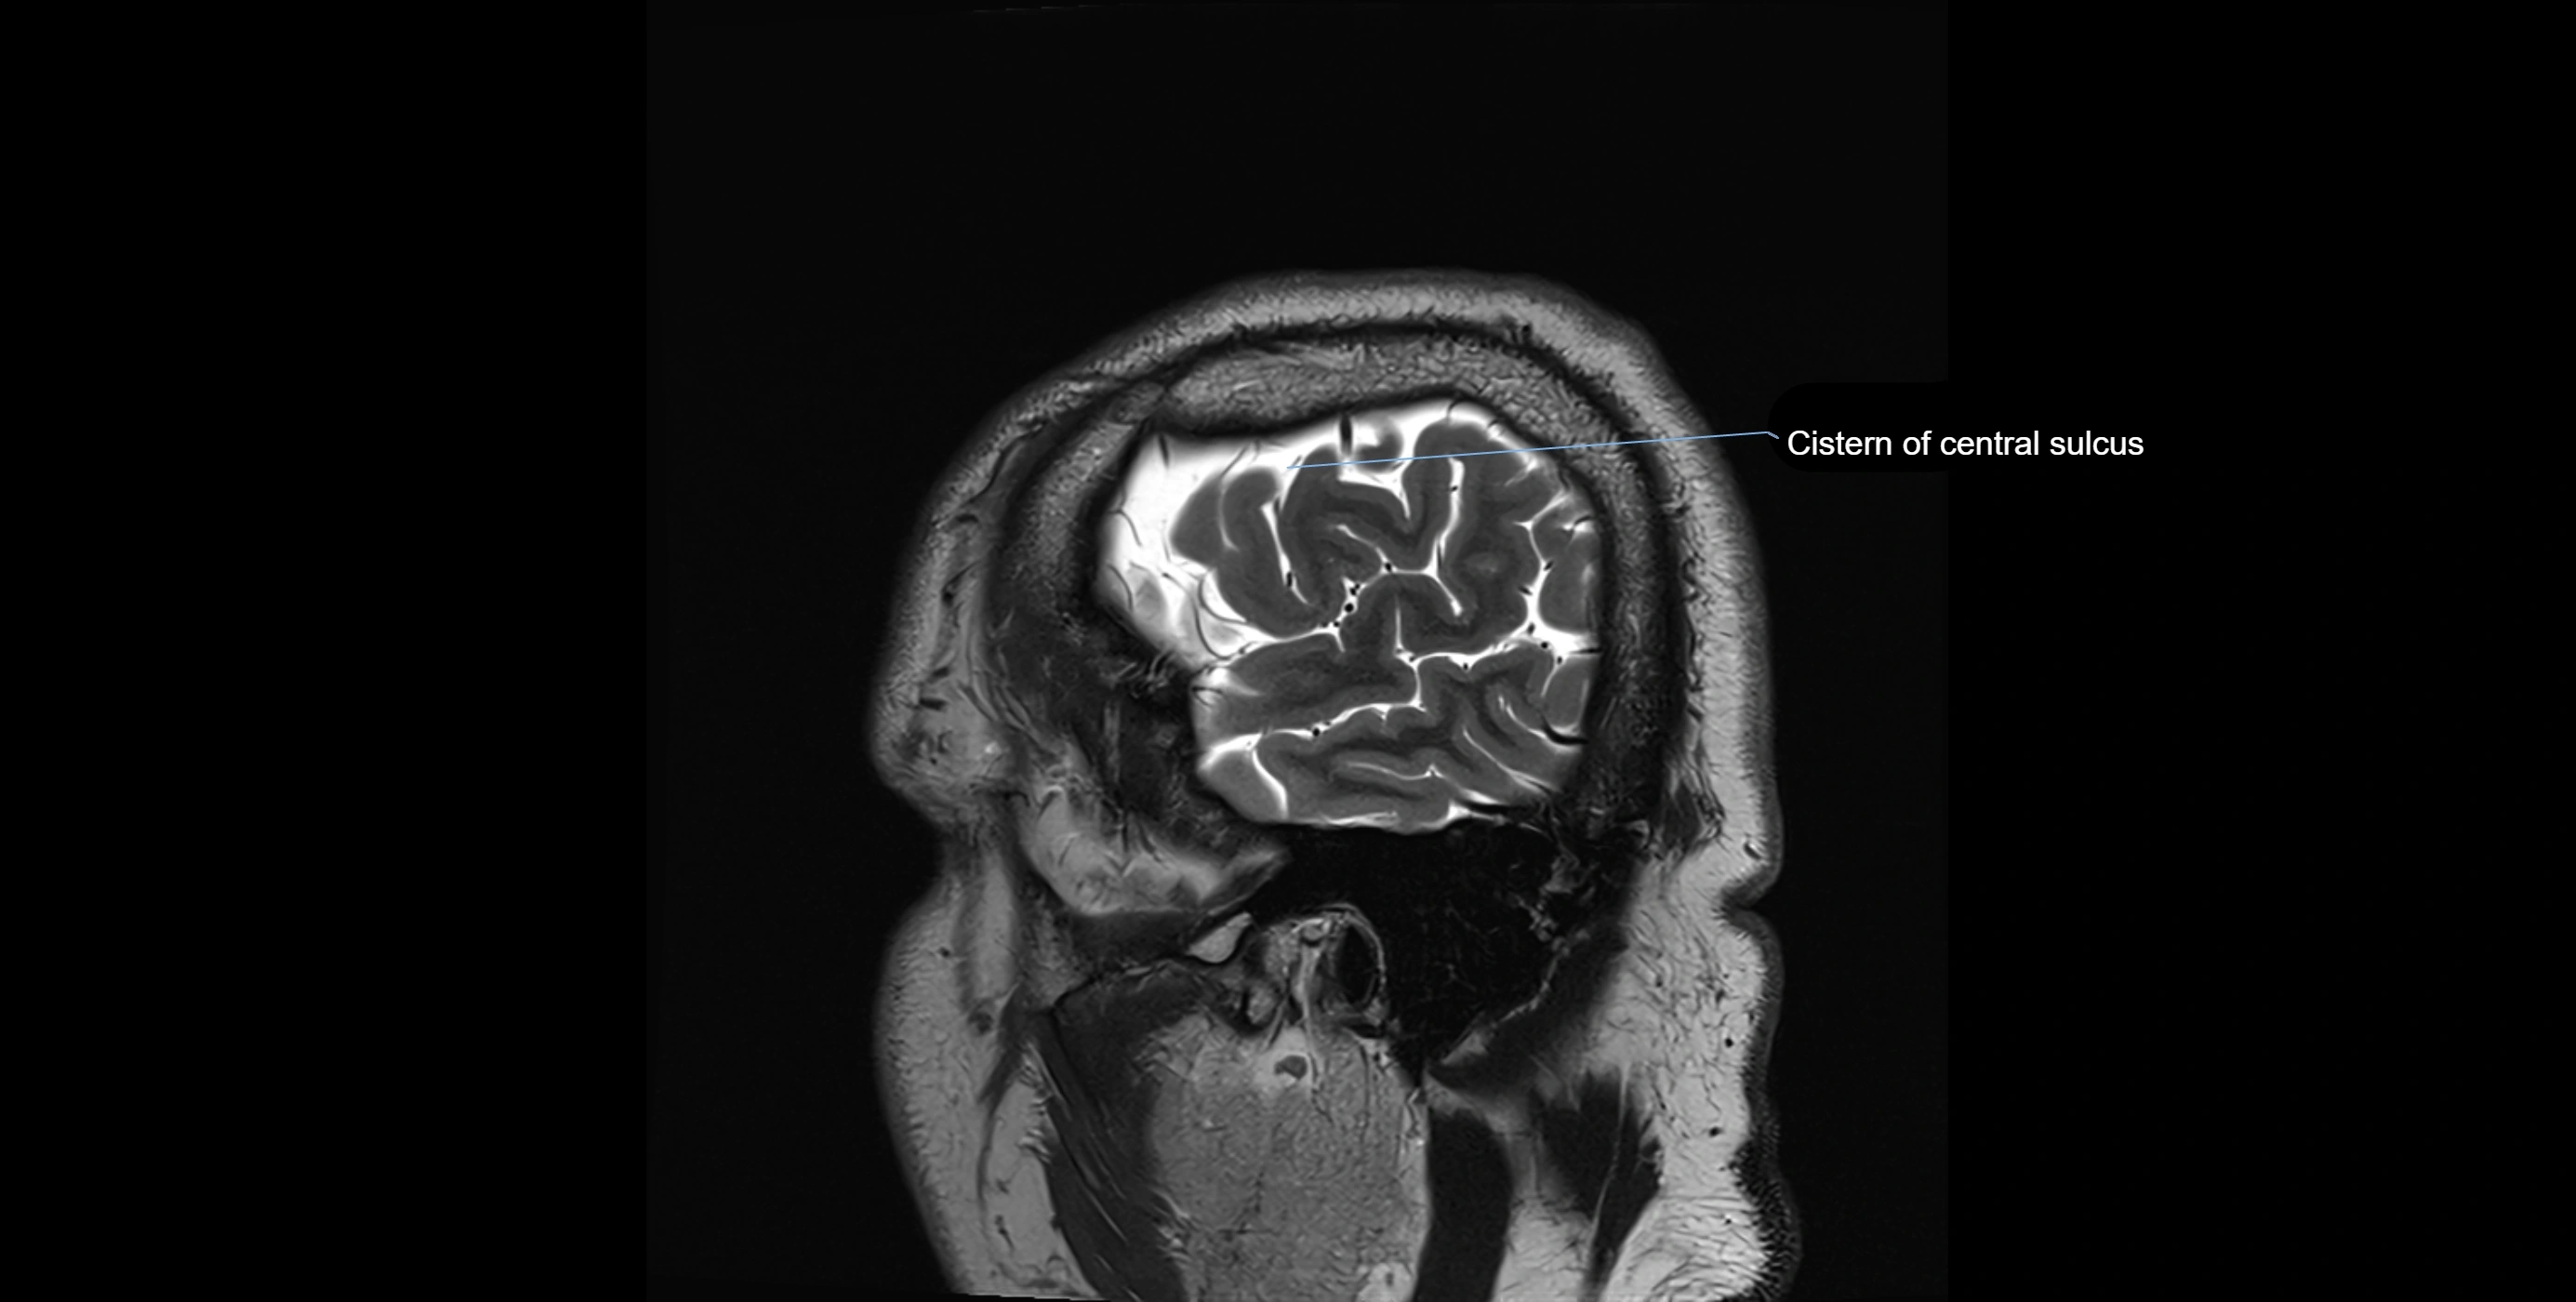

MRI images

image